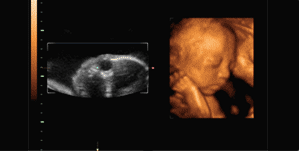

玛丽医生指出● 同其他超声诊断过程相比,四维彩超不再单纯依靠静态图像和某一时间点的结果作为诊断依据,而是实时观察宝宝的生存状况,更有利于医生判断胎儿发育情况,及时发现异常。

玛丽医生指出● 四维彩超能够立体地看到妊娠中晚期胎儿的全貌,多角度、全方位、连续动态的观察胎儿在腹中的情况,准爸准妈可以一同目睹宝宝在妈妈肚子里的一举一动和乖巧的面容。

玛丽医生指出● 四维彩超不仅可以获得结果照片,而且能够自动为胎儿进行宫内“写真”拍摄和动态录像,整个检查过程刻录成U盘就是“宝宝出演的一部微电影”了。

许昌更先进的四维彩超——GE-S6

许昌玛丽妇科医院拥有目前许昌的四维彩超监测仪——GE-S6四维彩超,它是利用出色的人体工程学设计,不存在辐射,对宝宝来说是的安全。与其它超声诊断过程相比,它可以实时的观察人体内部器官的动态运动,可以检测和发现各种异常。在目前超声领域,GE-S6四维彩超的畸形筛查、成像效果遥遥于其他设备。